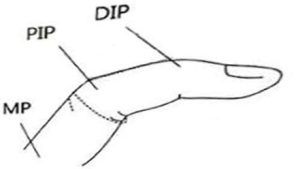

- تمرین ۴۰ درجه خم شدن ( فلکشن ) به صورت آرام و غیرفعال( پسیو) در مفاصل بین انگشتان نزدیک ( PIP) و دور (DIP)

شکل ۴. تمرین فلکشن مفاصل DIP و PIP